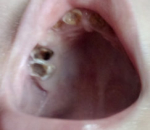

Сейчас же нам уже 2,2, и все четыре зуба разрушились совсем, одни корешки остались, и то черные, еще и заметила — шишечка какая-то вылезла на десне.

На этот вопрос правильно ответит доктор на очном приёме. Зуб, над котором шишка, скорее придётся удалить.